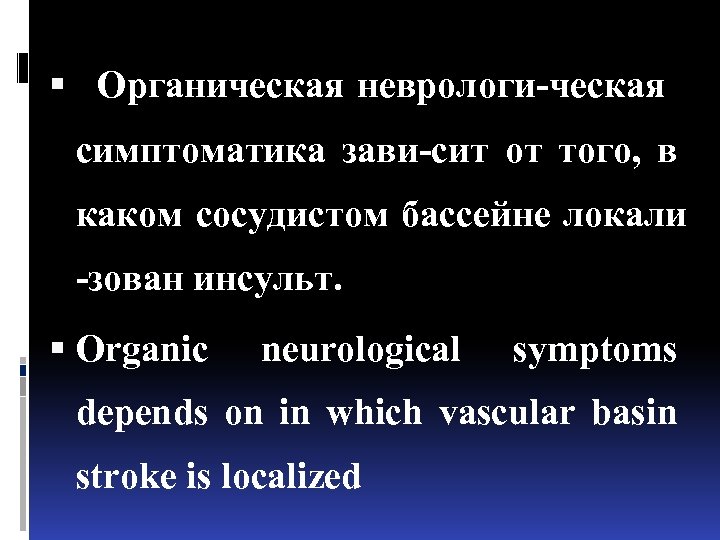

Органическая неврологи-ческая симптоматика зави-сит от того, в каком сосудистом бассейне локали -зован инсульт. Organic neurological symptoms depends on in which vascular basin stroke is localized

Органическая неврологи-ческая симптоматика зави-сит от того, в каком сосудистом бассейне локали -зован инсульт. Organic neurological symptoms depends on in which vascular basin stroke is localized